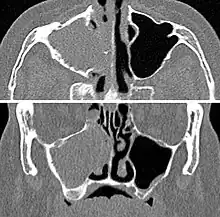

For sinusitis lasting more than 12 weeks, a CT scan is recommended.[47] On a CT scan, acute sinus secretions have a radiodensity of 10 to 25 Hounsfield units (HU), but in a more chronic state they become more viscous, with a radiodensity of 30 to 60 HU.[49]

-

CT of chronic sinusitis -

CT scan of chronic sinusitis, showing a filled right maxillary sinus with sclerotic thickened bone. -